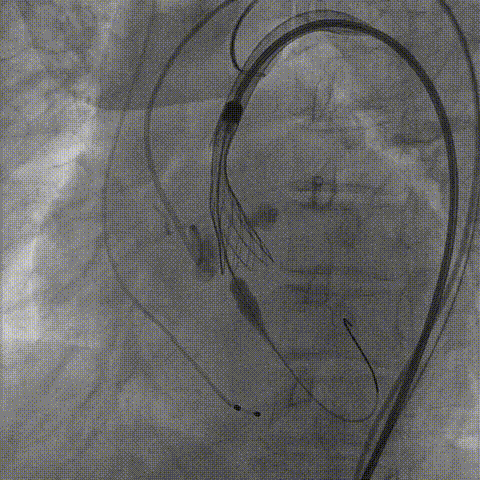

Snare协助输送器跨瓣

TaurusNXT植入过程

手术使用Z-Med 20mm球囊预扩两次,植入AV23 TaurusNXT主动脉瓣,Snare圈套器协助输送系统过弓、过瓣,120次/分起搏频率下,在左右重合位影像下释放瓣膜达到工作位,造影显示位置偏深,完全回收两次后释放达工作位,造影显示位置仍然不理想,之后第三次使用部分回收,精准释放瓣膜,之后使用Z-Med 20mm球囊后扩张两次。术后即刻超声心动图评估显示瓣膜位置良好,微量瓣周漏,主动脉瓣口峰值流速为1.90m/s,平均跨瓣压差为8mmHg,有效瓣口面积 1.60cm²,血流动力学指标理想。